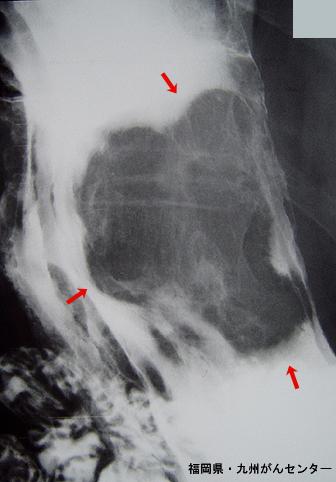

Criteria of Hist.ClassificationMalignant non-epithelilal tumors/Leiomyosarcoma (including GIST)

LocationStomach/Body

Technique, MethodX-ray

Size40 -